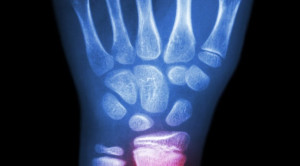

• Pendekatan Non-Operatif pada Lansia dengan Fraktur Radius Distal

Pendekatan Non-Operatif pada Lansia dengan Fraktur Radius Distal

Pendekatan non-operatif, misalnya dengan pembidaian, pada lansia dengan fraktur radius distal diduga dapat menjadi pilihan terapi yang lebih baik dibandingkan pembedahan pada...(Baca Selengkapnya)

• Imobilisasi pada Pasien Anak dengan Fraktur Torus Distal Radius – Telaah Jurnal Alomedika

Imobilisasi pada Pasien Anak dengan Fraktur Torus Distal Radius – Telaah Jurnal Alomedika

Immobilization of torus fractures of the wrist in children (FORCE): a randomised controlled equivalence trial in the UK Perry DC, Achten J,...(Baca Selengkapnya)